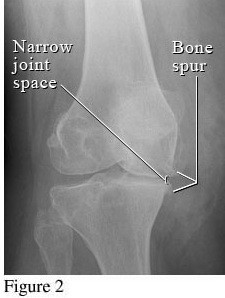

Hình ảnh so sánh giữa khớp bình thường và khớp bị thoái hóa khớp gối

Để phân biệt các giai đoạn của bệnh thoái hóa khớp gối, cần dựa vào phim X- quang theo tiêu chuẩn chẩn đoán thoái hoá khớp của Kellgren và Lawrence như sau: